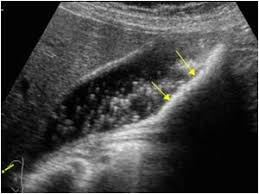

Small Kidney Stones In Ultrasound

Most scientist agree on the fact that ultrasound simply is not sufficient enough to detect very small kidney stones. Ultrasound can be efficient in visualizing clear uric acid stones and obstructions caused by any type of kidney stones. Ultrasound is frequently the first investigation of the urinary tract and although by no means as sensitive as ct it is often able to identify calculi.

Ultrasound is frequently the first investigation of the urinary tract and although by no means as sensitive as ct it is often able to identify calculi. What else can look like lots of small kidney stones in ultrasound. If your doctors are unclear about whether or not you have kidney stones they may want to do a ct scan which. Removing the kidney stone through a small incision in your back.